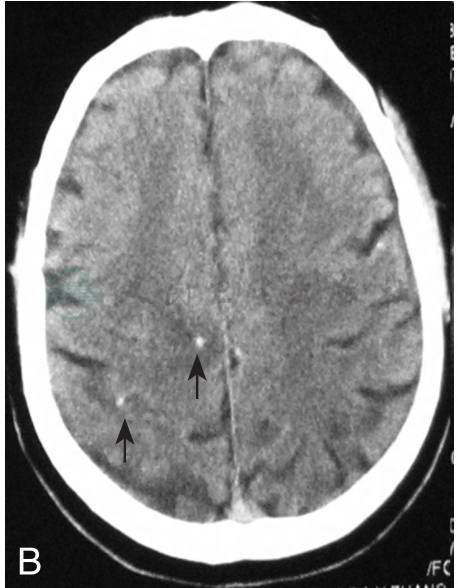

入院后完善检查,血常规、尿常规、粪便常规、凝血功能、HIV、乙肝五项、丙型肝炎病毒检查、血RPR均正常 。肝肾脂全:TC 6.47mmol/L,TG 2.35mmol/L,HDL-C 1.42mmol/L,LDL-C 4.01mmol/L。余正常。血CYT(+)。肿瘤指标:AFP、CA125、T-PSA、肺癌筛查均正常。血Hu-Yo-Ri:阴性。免疫指标:血C-RP、ASO、RF、ESR、ENA、ANCA均正常。血抗核抗体、抗双链DNA、ENA、ANCA阴性。心电图:窦性心律,未见异常。腹部B超:脂肪肝,双肾囊肿。超声心动图:左房增大,左室松弛功能减低。双下肢正位相:双下肢软组织可见钙化灶(图1)。行腰穿检查,压力210mmH2O,脑脊液常规:正常。生化:蛋白0.54g/L,糖3.1mmol/L,氯化物121mmol/L。CYT(+)。墨汁染色(-)。抗酸染色(-)。IgG合成率:-2.100mg/24h,未见瘤细胞。细胞学:正常。头CT:颅内多发高密度点状影。头MRI+DWI+MRS+增强:左额叶皮层下白质内小片状异常信号,与以前的摄片比较脑内多发皮层下白质异常信号较前明显吸收,左额叶皮层下异常信号较前减小;右额叶、右侧丘脑、右侧内侧颞叶结节状短T2信号,结合CT符合钙化表现;双额、左顶叶皮层下、右基底节多发慢性期腔梗。增强左额叶皮层下白质异常信号未见明显强化,右侧丘脑、右侧内侧颞叶异常信号可见异常强化,可符合脑囊虫表现。治疗上继续给予抗癫痫药物,给予阿苯达唑0.4g,每天2次,驱虫治疗14天,配合激素预防脑水肿。病情稳定,无抽搐发作。驱虫结束后复查头CT:脑室质内多发点状致密影无明显变化。患者出院随诊。

图1 A:小腿肌肉像可见点状钙化(黑箭头),提示既往囊虫感染后坏死虫体形成的钙化;B:头颅CT显示右侧顶叶的钙化灶(黑箭头),周围有低密度提示水肿;C:头颅MRI T2像显示右侧顶叶的病灶;D:头颅CT显示右侧颞角脑实质表面和脑室交界的圆形钙化灶